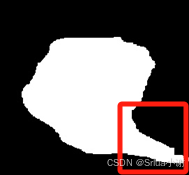

当跟踪到动脉血管后,我们对该目标区域进行分析,目标区域如下图所示。

但是这种算法有一个弊端,可以看出由于传统图像算法在进行分割时,往往会将红框中的非动脉区域错误分割,这也是不可避免的,所以我们提出了一种新的弹性分析算法。